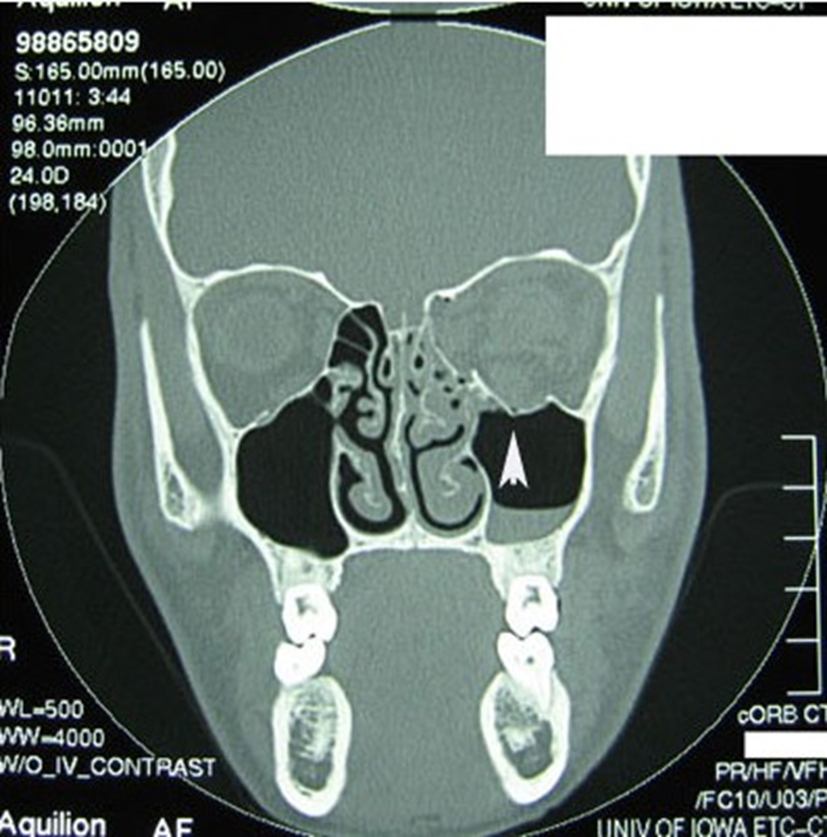

A CT scan of the eye socket is the best way to confirm an orbital fracture. Sometimes, if radiation is a concern, an MRI may be used instead.

Figure 3: CT scan showing a fracture with the arrow head.